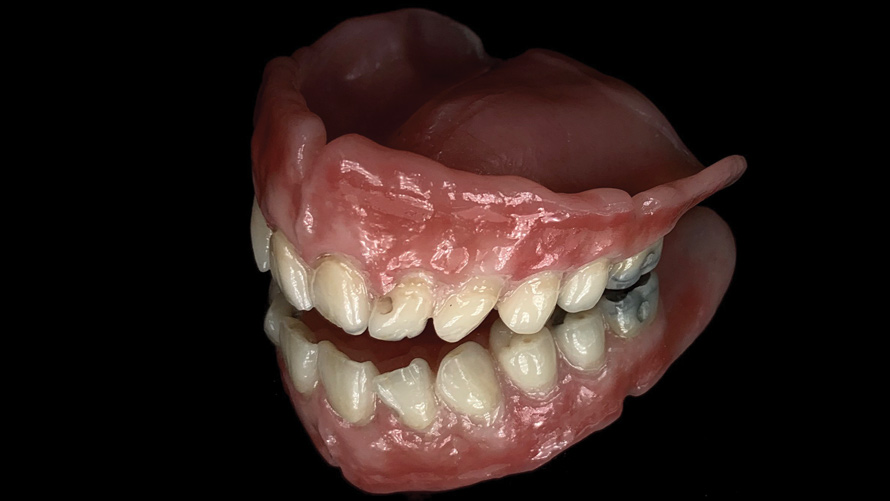

(9. through 11.) Preoperative esthetic case documentation using a smartphone and an EALS device.

Figure 9

Figure 10

Figure 11

One of the main advantages that smartphone cameras have over DSLR cameras is that nearly everyone is already very familiar with the technology; therefore, the incorporation of these devices into everyday practice does not require learning a new and unfamiliar skill set. The task of producing a series of high-quality clinical photographs for routine examinations (Figure 8), esthetic treatment planning (Figure 9 through Figure 11), or specialty care (Figure 12 and Figure 13) can be delegated with confidence to any staff member during the patient's initial office visit and will generally require less than 5 minutes of time to complete. When a DSLR camera is used, evaluation of the intraoral images either takes place on the small viewfinder built into the camera or necessitates the physical removal of the memory card from the camera to downloaded the images onto a computer for review. An added bonus of smartphone dental photography is that the phone's screen now replaces the much smaller viewfinder of a DSLR camera and provides the clinician with the ability to view and zoom into the patient images on a 5- to 6-inch, high-definition display.